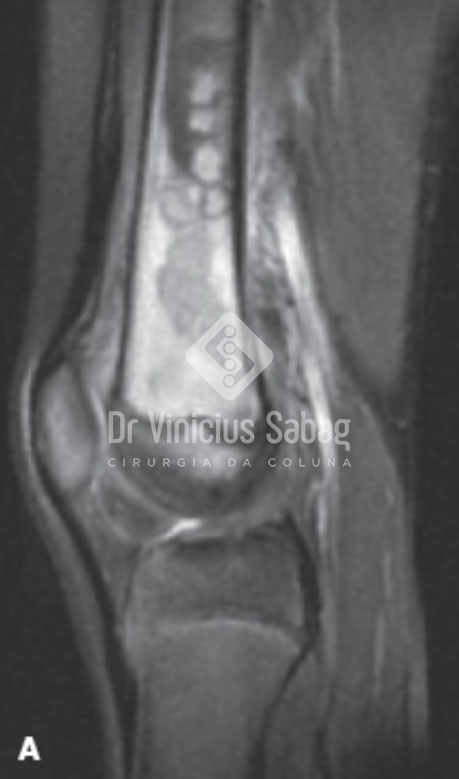

Ressonância magnética evidenciando osteomielite no fêmur .